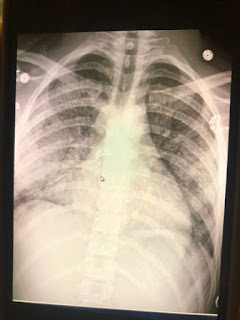

A chest X-ray of Adam Hergenreder's lungs revealed inflammation, likely from vaping, according to doctors at Advocate Condell Medical Center in Libertyville, where the 18-year-old from Gurnee was hospitalized Aug. 31. Hergenreder is one of dozens hospitalized across Illinois, and hundreds across the country, for a respiratory illness likely linked to vaping.

Now Hergenreder, of Gurnee, is hospitalized and unable to breathe without a steady flow of oxygen through tubes affixed to his nostrils. Doctors have told the 18-year-old that images of his lungs from a chest X-ray look like those of a man in his 70s. His lungs may never be the same again, and vaping is likely to blame.